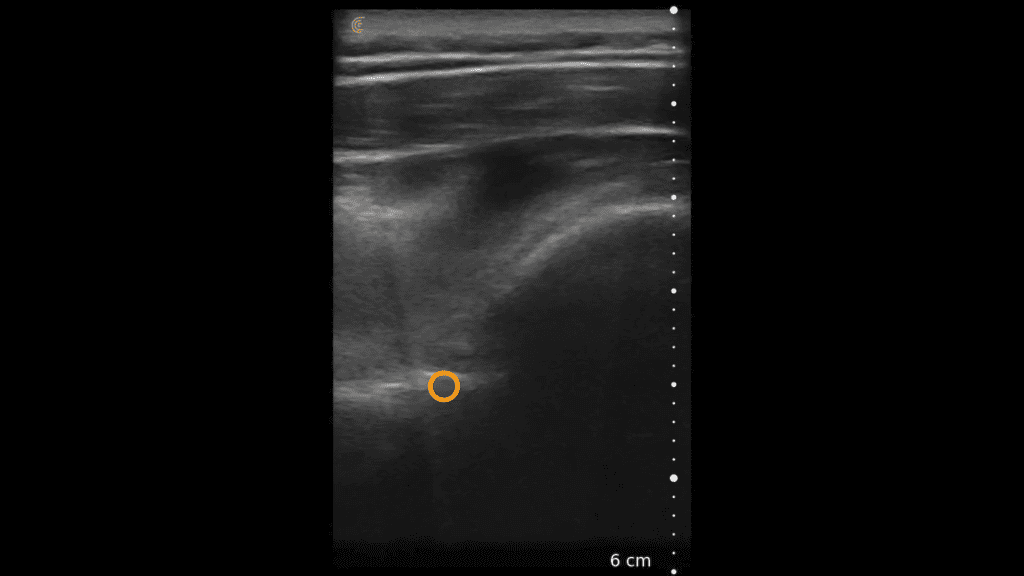

Using the jejunum as an important landmark, the hypoechoic jejunal lymph nodes can be identified. In this video Dr. Edwards explains the ultrasound appearance of normal jejunal nodes.